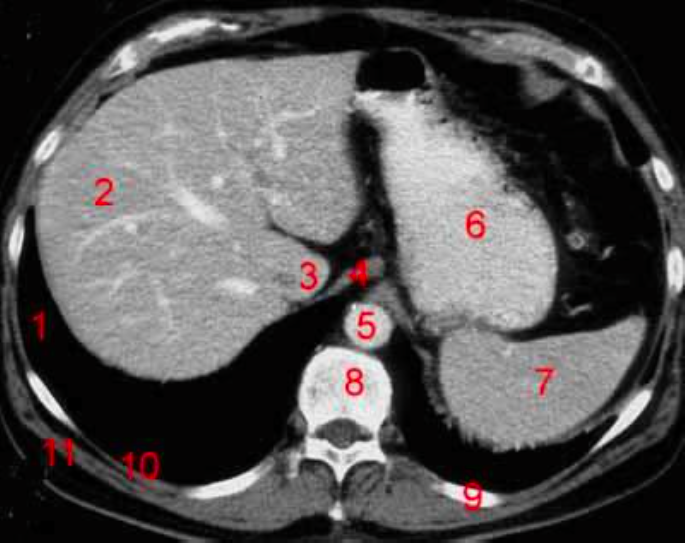

10

Number 8?

Descending colon

11

Number 2?

Rt lobe of liver

16

IVC

17

Number 4?

Rt lobe liver

18

Number 1?

R lung

19

20

Number 6?

Stomach

27

Number 7?

Spleen

39

41

Number 5?

L Ventricle